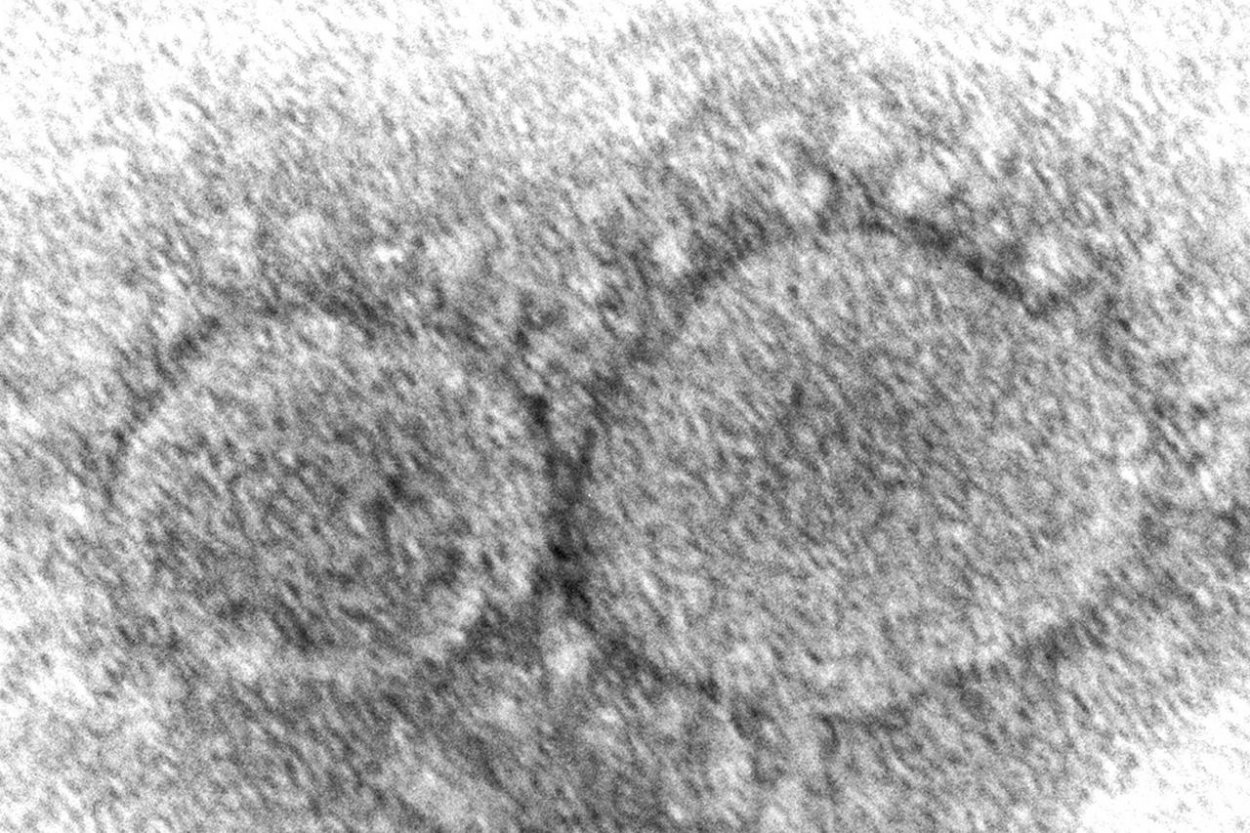

Prvýkrát si pripomenieme na Slovensku Deň obetí pandémie covid-19 Hannah A. Bullock, Azaibi Tamin/CDC via AP

Dátum 6. marec bol zvolený preto, lebo 6. marca 2020 sa na Slovensku potvrdil prvý prípad nákazy koronavírusom SARS-CoV-2, ktorý spôsobuje ochorenie covid-19. Infikovaný bol 52-ročný muž z Kostolišťa pri Malackách.

Prvým človekom s vírusom SARS-CoV-2 na svete bol 55-ročný muž z čínskej provincie Chu-pej, ktorý sa nakazil už 17. novembra 2019. Práve z metropoly tejto provincie Wu-chan sa smrteľný koronavírus postupne rozšíril do celého sveta a spôsobil pandémiu. Podľa údajov Svetovej zdravotníckej organizácie (WHO) si na celom svete vyžiadal už takmer 7 miliónov obetí.